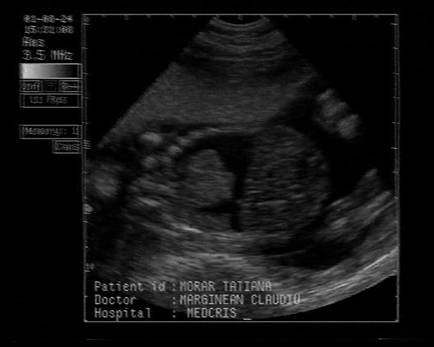

Fig . nr. 248. Chist de plex choroid , unilateral, la o sarcina de 17 sapt.

Fig. nr. 249. Hidrocefalie interna unilaterala aparuta la 28 sapt si cu evolutie rapida, postpartum se confirma suspiciunea de diagnostic: hemoragie cerebrala